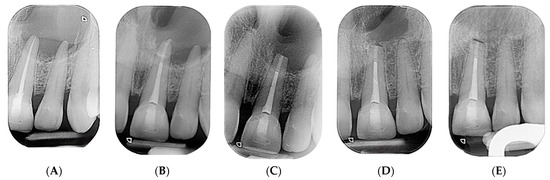

2.2. Delivery of Treatment

2.4. Healing of the Defect and Follow Up